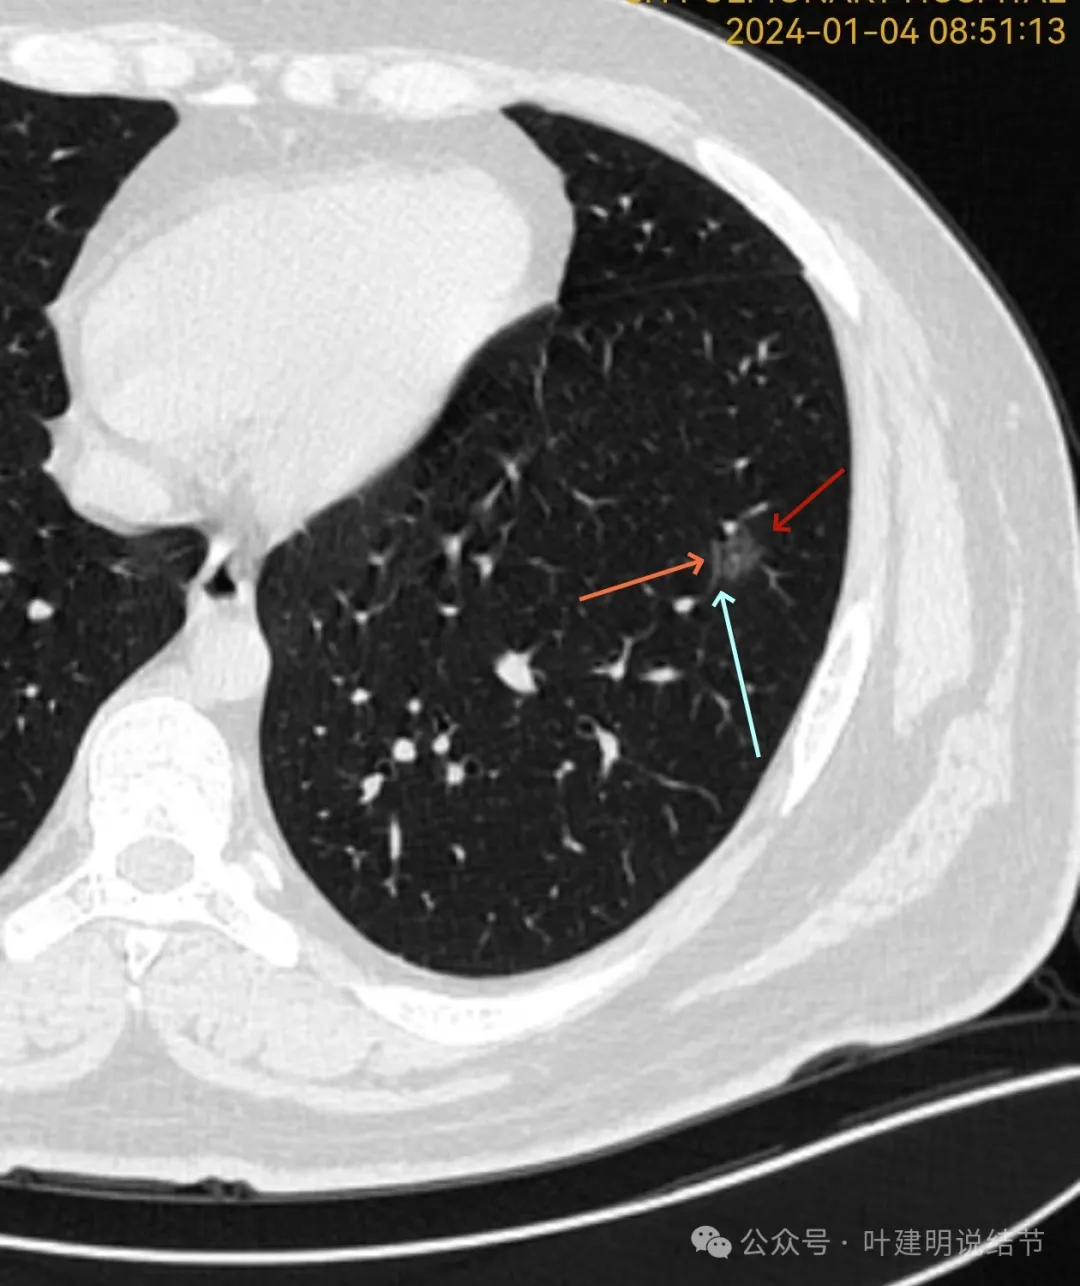

我们先来看2024年1月份的影像最明显的层面:

病灶磨玻璃密度,不太纯,轮廓清楚,灶内有小空泡征,整体轮廓与边界清楚。

血管贴边,病灶与血管间间隙不太明显,灶内密度稍显不均。